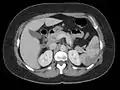

Echocardiography is the main diagnostic tool for LVT. A distinct mass is visible in the left ventricle. Computed Tomography and Magnetic Resonance Imaging are effective, but less common ways to detect LVT, due to their costs and risks.[1] It is possible to assess whether a thrombus will become an embolus through echocardiography. Mobility and protrusion of the thrombus are two characteristics associated with increased embolic potential.[8]